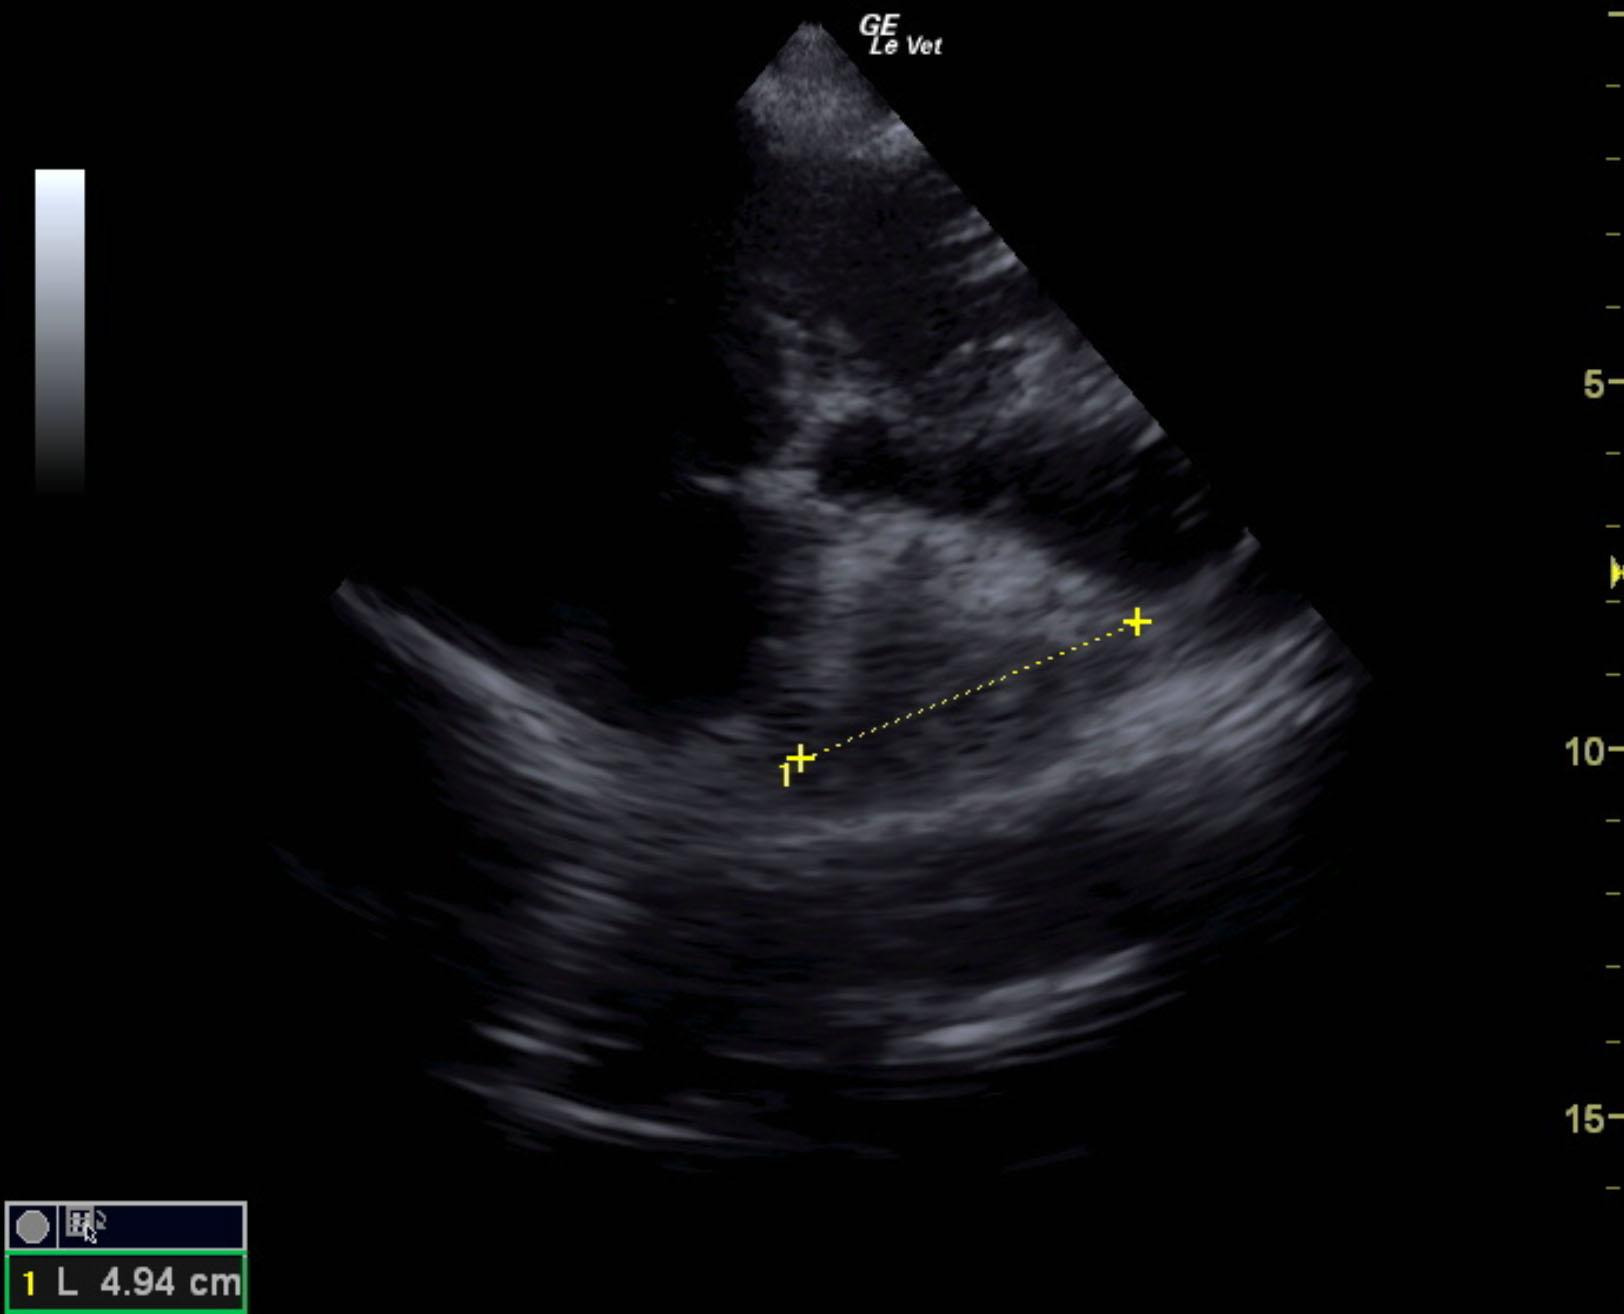

The patient is a canine Mastiff, male, 1 year old who was presented for surgery for the eye, however physical exam revealed muffled heart sounds. Radiographs revealed mass at the heart base.